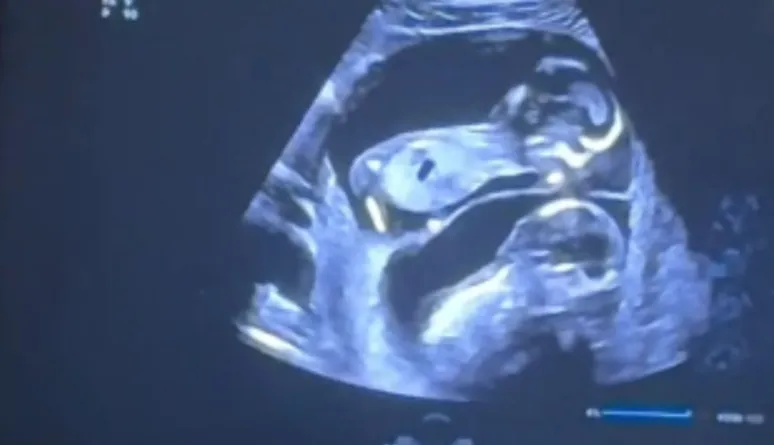

Upon their return to Texas, they made the decision to try artificial insemination. A few weeks later, Lauren took a pregnancy test that turned their world upside down—she was pregnant. But the news didn’t stop there. During a routine ultrasound, Lauren and Dave learned they were expecting sextuplets. The doctor’s words were clear but overwhelming: six babies.

The news was a shock, not just for Lauren and Dave, but for their doctors as well. Carrying six babies put Lauren at extreme risk, and doctors warned of potential complications, including pre-eclampsia and premature birth. But despite the challenges, Lauren’s determination never wavered. She and Dave were ready to face whatever came their way.